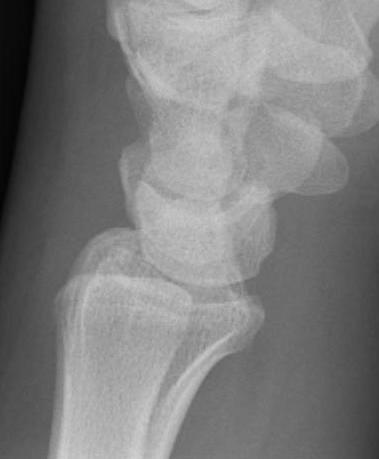

Scaphoid waist fracture 1 mm displaced

Scaphoid fracture with significant displacement

Scaphoid proximal pole fracture